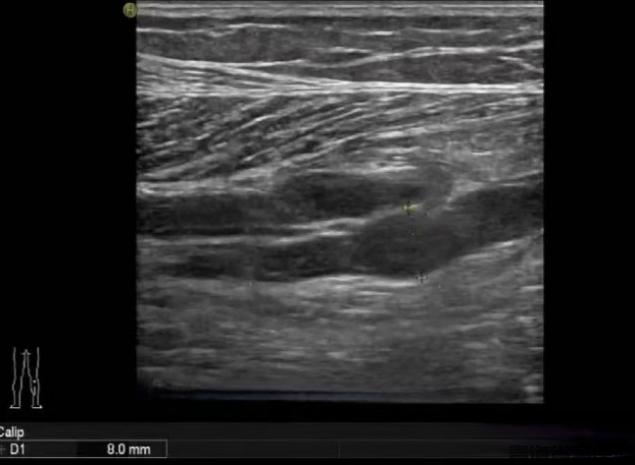

图片3.png

图片4.png

常规二维灰阶超声检查

小腿肌间静脉管腔扩张,充满低回声,探头加压无法压扁,提示血栓形成

彩色多普勒超声检查

管腔内未见彩色血流信号,进一步提示静脉管腔内血栓形成